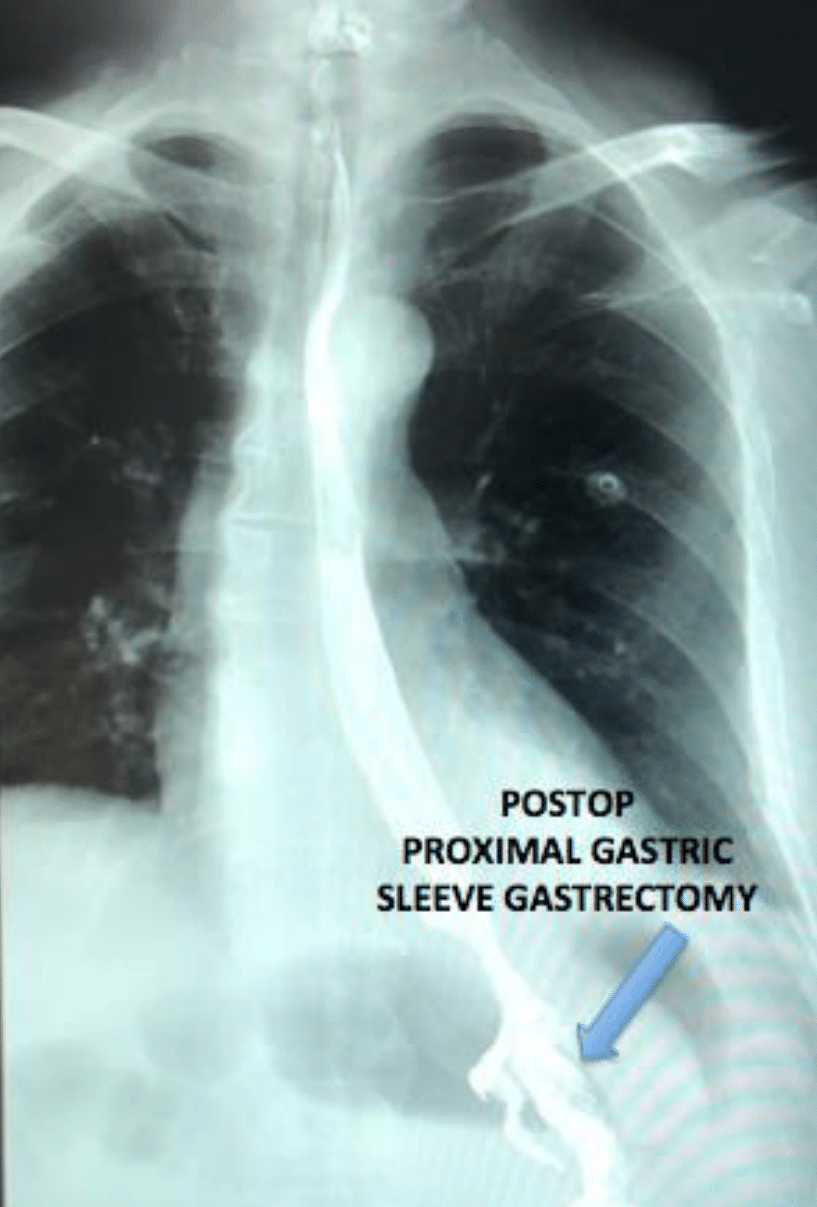

A 73-year-old male patient with a history of laparoscopic bilateral inguinal hernia repair twenty years before, and laparoscopic antireflux surgery 18 years before. Eleven years later he presented episodes of belching, heartburn, and continuous fermented food smell which were progressive. Endoscopy at that time revealed a large paraesophageal hiatal hernia which was treated with proton pump inhibitors, prokinetic medication, and dietary restrictions. His symptoms progressed until he was almost unable to eat, and came to the clinic due to intense continuous postprandial substernal pain and dysphagia. An endoscopy and an upper gastrointestinal (GI) series were performed, which showed a giant HH with a complete thoracic gastric volvulus. He underwent a laparoscopic procedure, performing hiatal repair with mesh placement and a Nissen fundoplication, which corrected the symptoms. Five months later, he presented again an acute intense substernal pain, significant upper abdominal distention, profuse salivation, and severe dysphagia. The upper GI series revealed a giant recurrent HH and a mesenteroaxial gastric (Figure 1) volvulus with complete obstruction to distal pass of contrast media. Due to his medical history, evident weakness of the hiatal tissues, and the possibility of a new recurrence, it was discussed with the patient to perform a PSG of the gastric body and fundus to lengthen the esophagus, which was accepted by the patient and his family. By laparoscopy, the herniated gastric volvulus (Figure 2) was reduced and a PSG was performed leaving the hiatus open (Figure 3). The mesh was left in situ as it was completely epithelized. His postoperative recovery was adequate, the postoperative upper GI series showed adequate transit of the contrast medium (Figure 4). Two years after this surgery he is well, does not report any symptoms related to reflux or dysphagia, doesn’t take any medications, his diet is normal and he carries out his daily activities normally.

Figure 4 Postop upper GI series with adequate transit through the proximal sleeve gastrectomy.